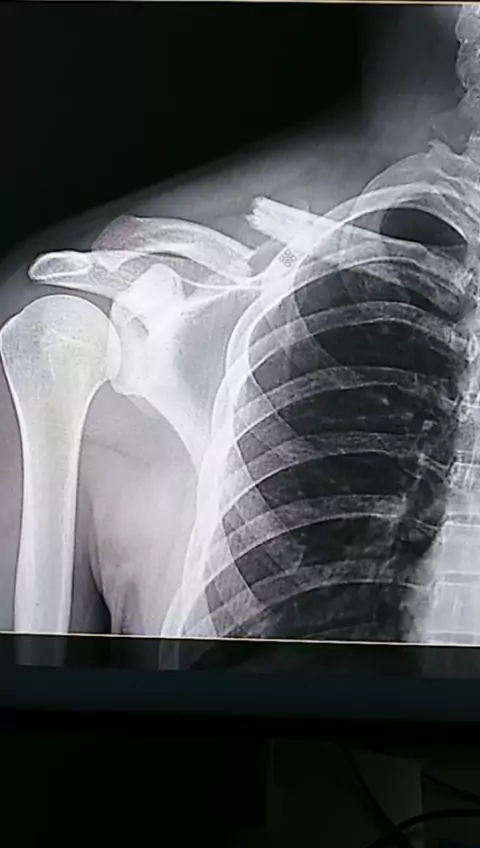

Fratura da clavícula✅💀☢ #Radiologia